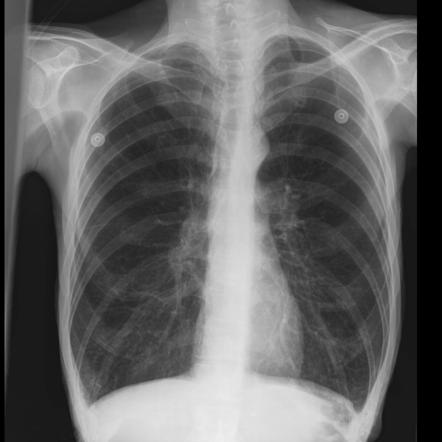

- Chest x-ray

- CT scan